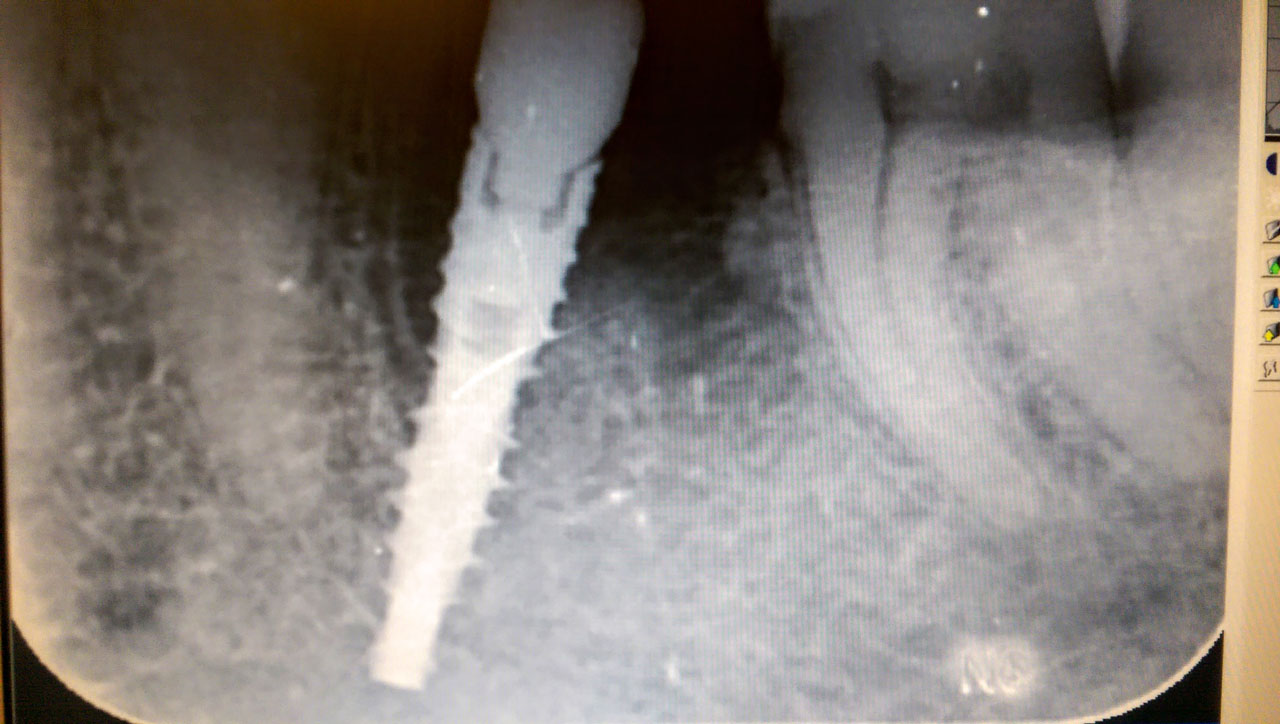

Az azonnal terhelhető implantátum nem okoz csalódást

A forradalmi újítások képesek növelni a társadalom általános életminőségét. Az orvosok esküjükhöz hűen mindig azon fáradoznak, hogy mindenkit meggyógyítsanak. Az azonnal terhelhető implantátum fantasztikus újítás, ami az utóbbi 10 évben ért el arra a szintre, amit ma is alkalmaznak.

A híres svájci doktor Stephan Ihde alkotta meg ezt az egész rendszert és természetesen róla is lett elnevezve az azonnal terhelhető implantátum. Ma már a legtöbb szakember folyamatosan próbálja tartani a versenyt ezekkel az innovatív technológiákkal, de ez a sikeresség szempontjából is kiemelten fontos. Ez a különleges beültethető elem speciális tudást és eszközöket igényel, tehát csakis azok vállalnak ilyesféle munkát, akik rendelkeznek a megfelelő minősítéssel. Az azonnal terhelhető implantátum a leggyorsabb módja annak, hogy Ön új mosolyt kapjon.

Ha érdekli ez az eljárás, akkor ajánljuk, hogy nézzen be a dentalcenterkelemen.hu internetes felületre, amit a budapesti Relax Dental Center üzemeltet! Az érdeklődők ezen a portálon keresztül megismerkedhetnek az azonnal terhelhető implantátummal.